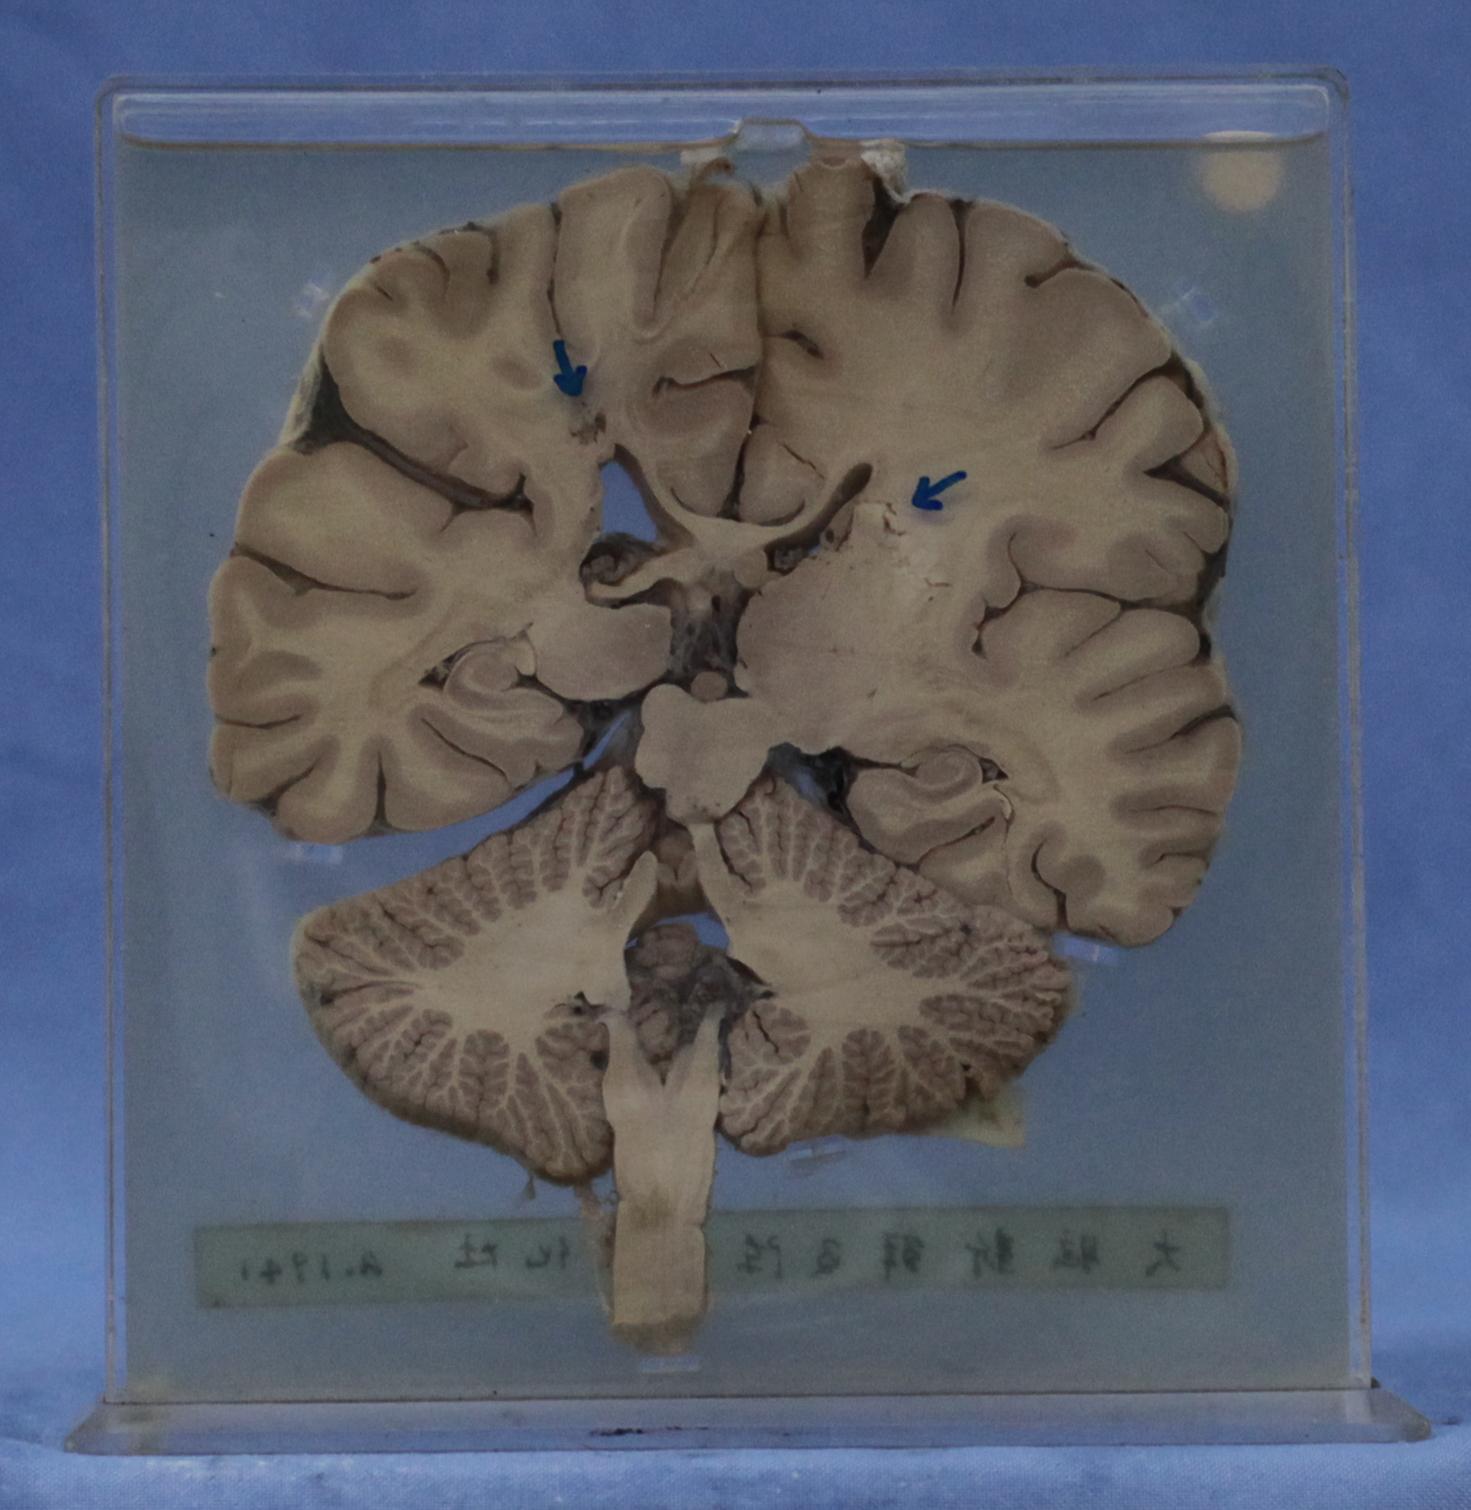

神经疾病-59-20. 大脑液化性坏死

大脑半球、小脑及延髓冠状切面,在双侧基底节与胼胝体相连部位分别见一直径0.5cm液化坏死灶(左),0.5-0.8cm(右)液化坏死灶。